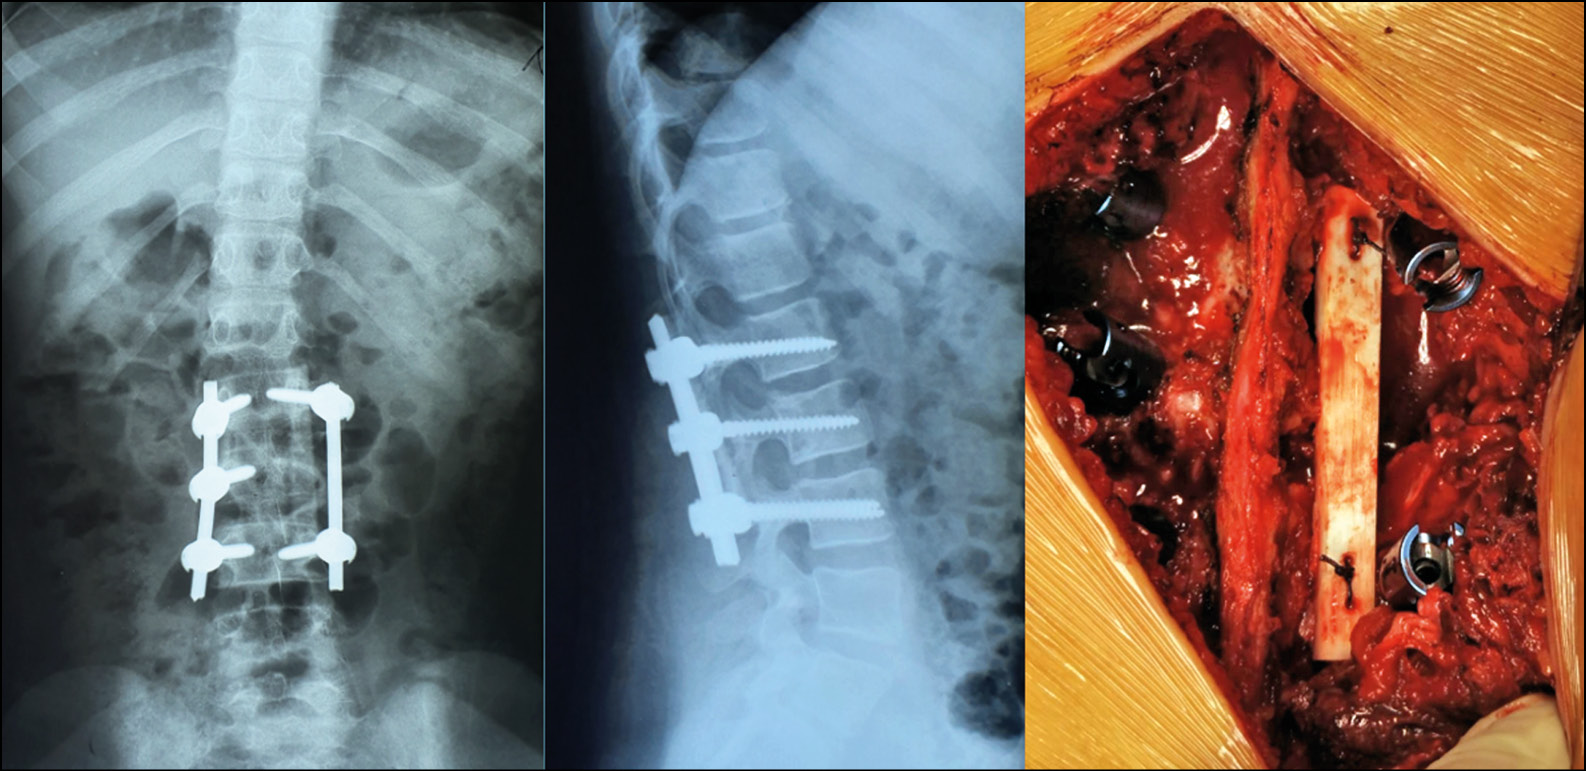

Клинический пример — пациентка 15 лет.

Обратилась по месту жительства с болями в поясничном отделе позвоночника. При попытке консервативного лечения, боли резко усилились. При дообследовании по данным КТ и МРТ поясничного отдела позвоночника выявлено патологическое образование в L3 позвонке с формированием стеноза позвоночного канала (рис. 3).

Рис. 3. КТ и МРТ исследования при поступлении

Fig. 3. CT and MRI examinations upon admission

При проведении Лечебно-диагностической пункции получено высокое давление (242 мм водного столба). Отправленный на гистологическое исследование материал подтвердил диагноз аневризмальная киста позвонка L3. Проводились повторные пункции с интервалом в 1.5 месяца. После 3 манипуляции отмечено стойкое снижение болевого синдрома, снижение степени активности кисты и стеноза позвоночного канала.

По данным КТ исследований отмечены признаки частично репарации костной ткани позвонка (рис. 4). Далее было проведено открытое хирургическое вмешательство (рис. 5) в объёме — ТПФ на уровнях L2-4 позвонков, гемиламинэктомия L3 справа, удаление оболочек анверизмальной кисты, декомпрессия позвоночного канала., комбинированная пластика костного дефекта с применением ауто- и аллотрансплантатов. Время хирургического вмешательства составило 2 ч. 15 мин. Объём кровопотери — 240 мл.

Рис. 4. КТ и МРТ через 5 месяцев на фоне проведенного пункционного лечения с менее выраженным стенозом содержимого позвоночного канала

Fig. 4. CT and MRI results after 5 months of puncture treatment with less pronounced stenosis of the spinal canal

Рис. 5. Рентген после хирургического вмешательства и внешний вид послеоперационной раны

Fig. 5. X-ray after surgery; the postoperative wound

Пациентка вертикализирована на 3 сутки в ортопедическом ортезе с фиксацией поясничного отдела позвоночника. Болевой синдром полностью купирован на 5 сутки. При динаммческом наблюдении в течении 1,5 лет (рис. 6). Признаков рецидива не выявлено. Костный блок сформировался на 9 месяц с момента операции. При КТ исследовании отмечена стабильность металлофиксации, отсутствие признаков рецидива патологического процесса, интеграция в костный блок аллотрансплантата, а так же восстановление костной ткани по типу «памяти формы».

Рис. 6. КТ зоны операции через 1,5 лет с момента хирургического вмешательства

Fig. 6. CT scan of the operation area in 1.5 years after surgery

Учитывая возраст пациентки и отсутствие выраженного продолженного роста позвоночного столба (Risser 4) показаний к удалению металлоконструкции на момент последнего наблюдения не выявлено.